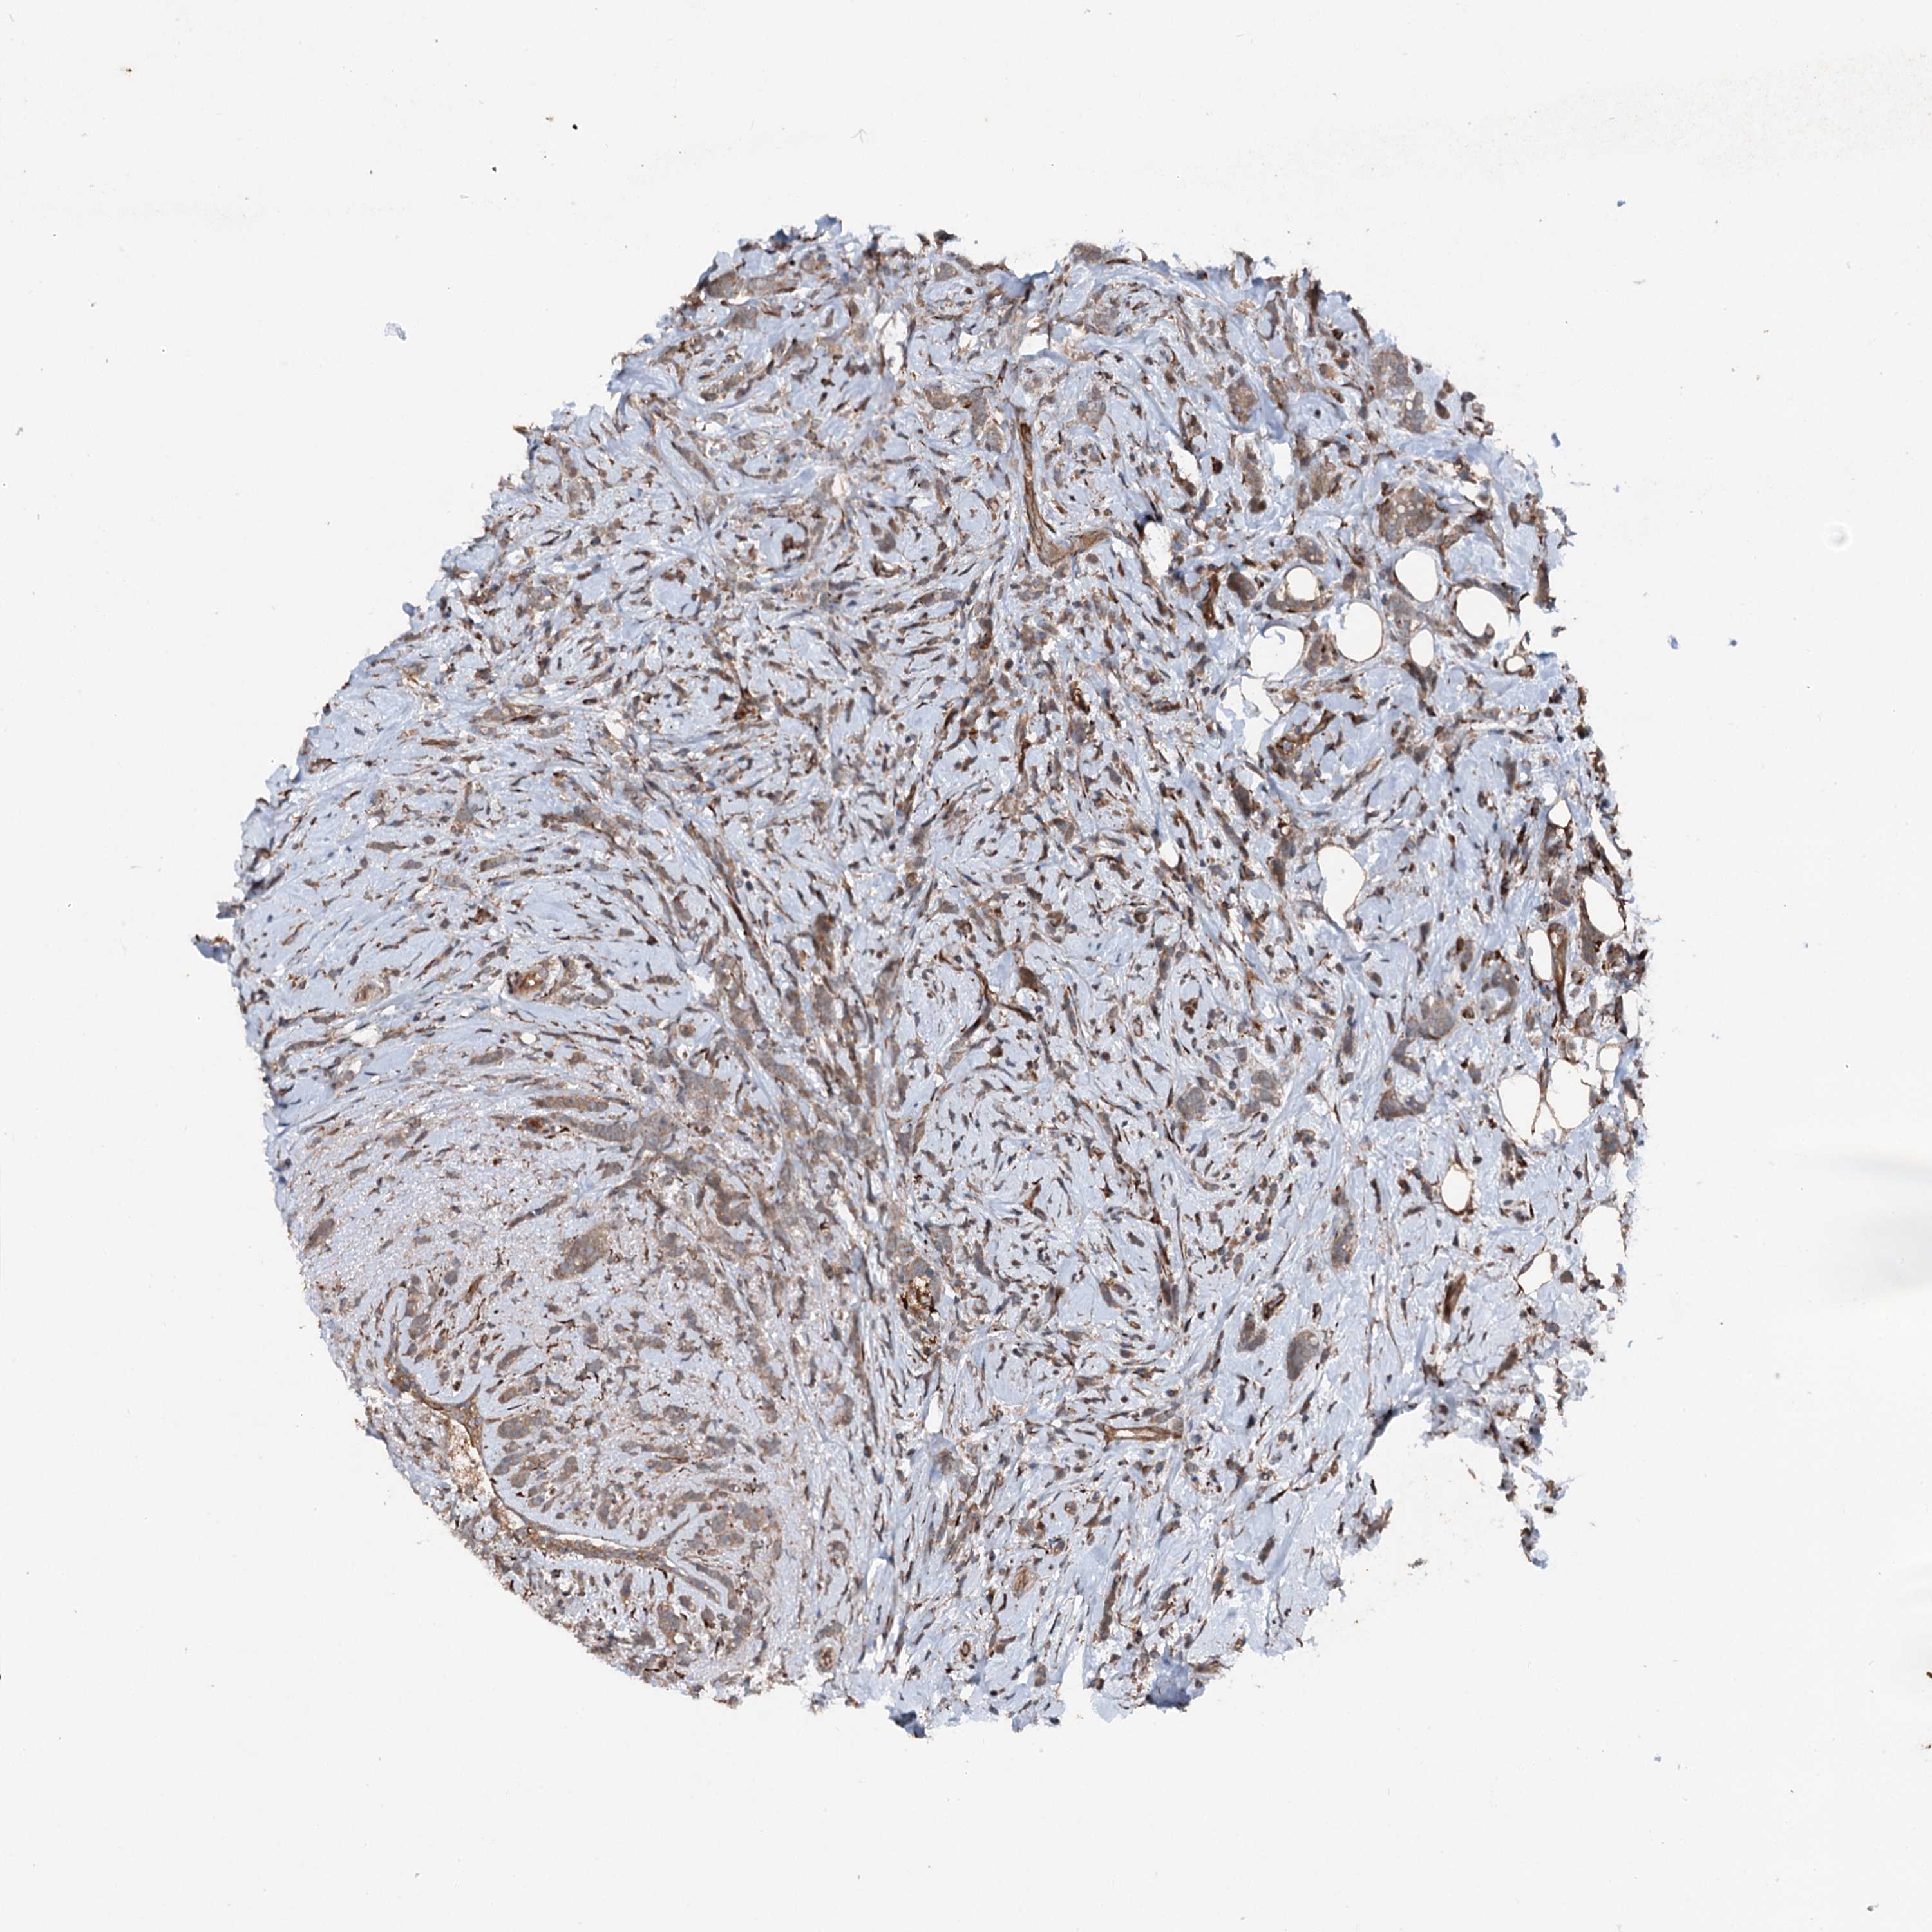

BRCA TCGA BRCA VALIDATION PROTEIN EXPRESSION